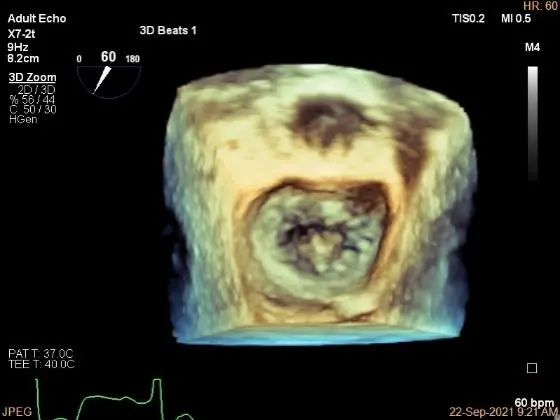

3D:P1区脱垂并腱索断裂,Width:11.4mm

3D-color:重度MR,4级

3d确认夹子位置在P1区

3d-color确认残余分流情况